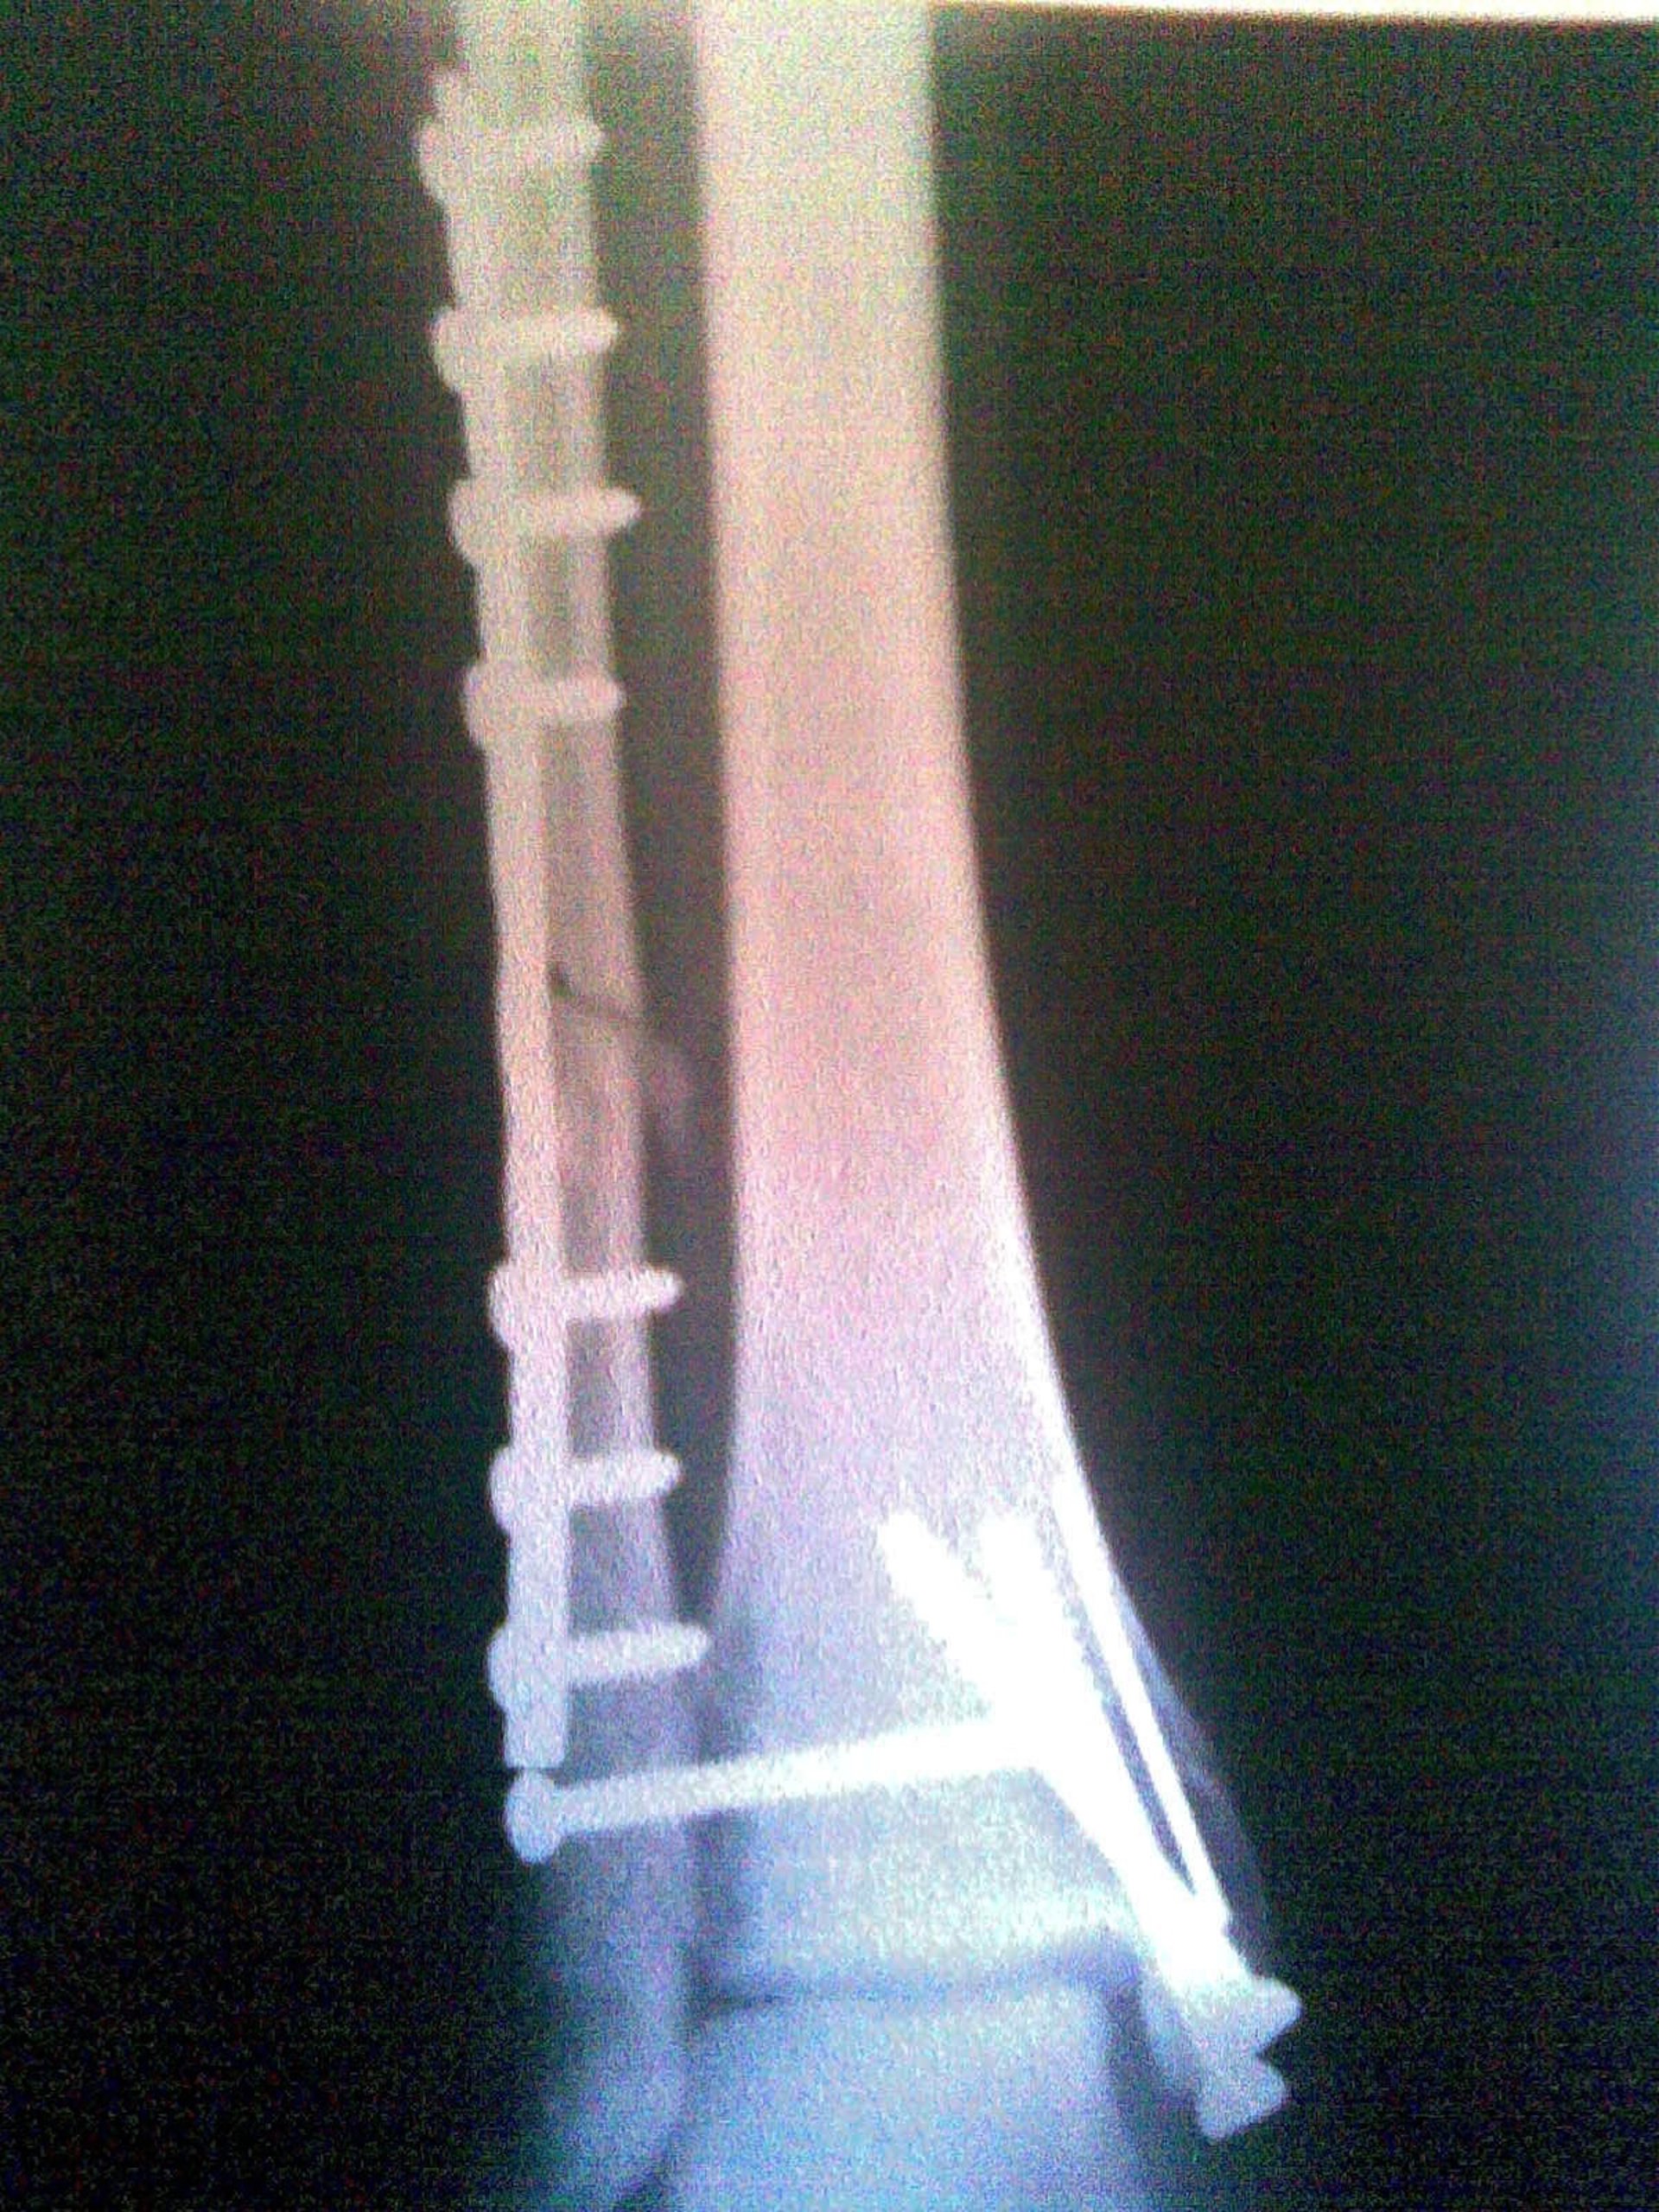

Radiografia, Hueso

Según unos datos facilitados por la SERAM en estas jornadas, el 85 por ciento de los diagnósticos médicos que se realizan en la actualidad se basan en pruebas de imagen como los rayos X, las ecografías, las resonancias magnéticas o la tomografía computarizada (TAC).